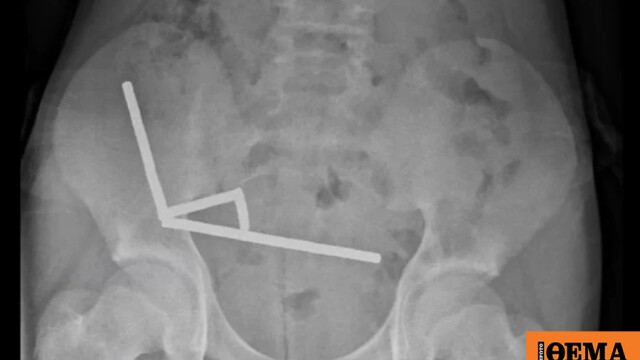

Μέχρι και 100 ισχυρούς μαγνήτες που είχε αγοράσει από το Ίντερνετ κατάπιε 13χρονος από τη Νέα Ζηλανδία, με αποτέλεσμα να νεκρωθεί μέρος από τα έντερά του.

Εκεί οι γιατροί διαπίστωσαν ότι είχε καταπιεί περίπου 80 με 100 μαγνήτες νεοδυμίου διαστάσεων 5 επί 2 χιλιοστών περίπου μία εβδομάδα νωρίτερα, ανέφερε έκθεση του…